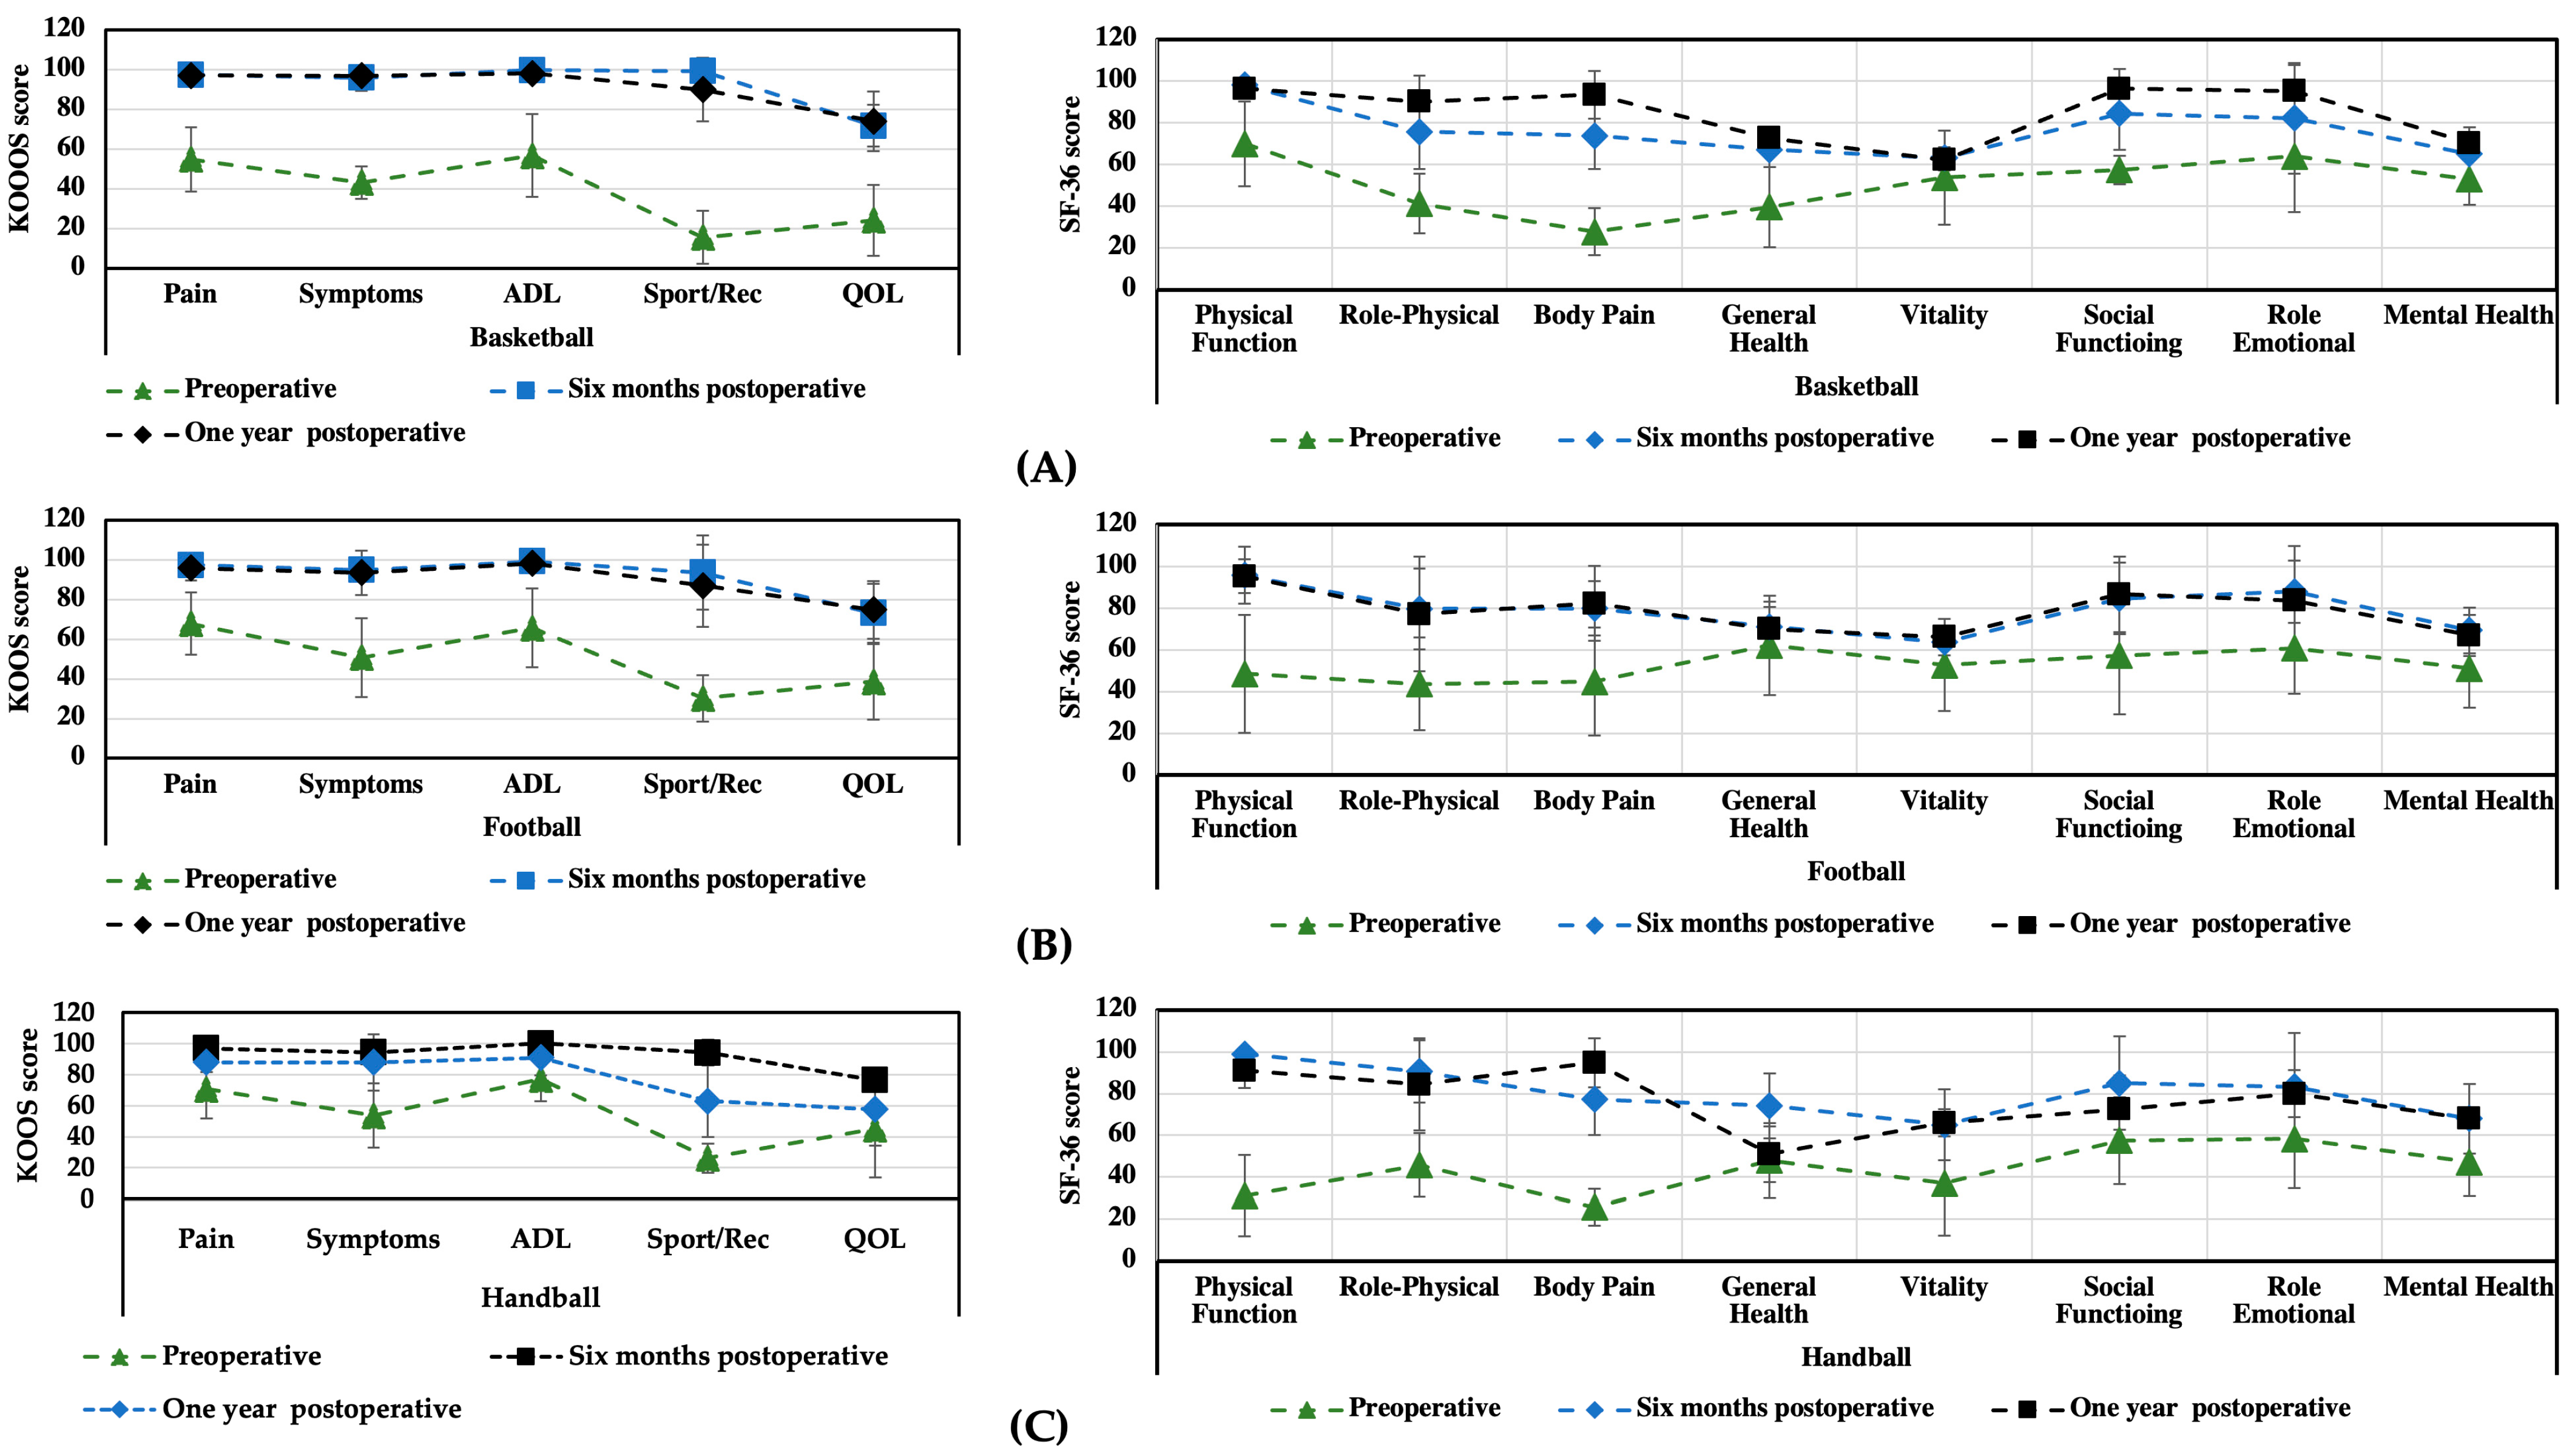

3.1. KOOS and SF-36 Scales

| Preoperative | Six Months Postoperative | One Year Postoperative | (before/after Six Months) | |

|---|---|---|---|---|

| KOOS | Mean ± SD | Mean ± SD | Mean ± SD | p |

| Patients (n) | 49 | 49 | 43 | |

| Pain intensity | 55 ± 18.2 | 96 ± 4.2 | 99.5 ± 2.3 | <0.05 |

| Symptoms | 46 ± 16.6 | 93 ± 6.5 | 98.2 ± 1.8 | <0.05 |

| Activities of daily living | 57 ± 25.5 | 99 ± 2.6 | 100 ± 0.0 | <0.05 |

| Sport/Rec | 14 ± 11.1 | 95 ± 7.7 | 99.8 ± 1.8 | <0.05 |

| Quality of life | 30 ± 18 | 76 ± 4.7 | 88 ± 8.8 | <0.05 |

| Preoperative | Six Months Postoperative | One Year Postoperative | ||

|---|---|---|---|---|

| SF-36 | Mean ± SD | Mean ± SD | Mean ± SD | (before/after Six Months) |

| Patients (n) | 49 | 49 | 43 | p |

| Physical function | 34 ± 18.5 | 95.6 ± 2.0 | 97 ± 2.5 | <0.05 |

| Role physical | 63 ± 46.5 | 76 ± 15.0 | 96 ± 3.7 | 0.345 |

| Bodily pain | 36 ± 18.7 | 78 ± 15,6 | 98 ± 2.3 | <0.05 |

| General health | 68 ± 17.1 | 70 ± 16.1 | 83 ± 15.8 | 0.401 |

| Vitality | 53 ± 20.6 | 64 ± 8.0 | 87 ± 7.1 | 0.067 |

| Social function | 64 ± 29.6 | 87 ± 13.6 | 90 ± 9.5 | 0.068 |

| Role emotional | 73 ± 42.0 | 83 ± 22.9 | 90 ± 13.3 | 0.285 |

| Mental health | 52 ± 9.8 | 68 ± 11 | 70 ± 10.8 | 0.464 |